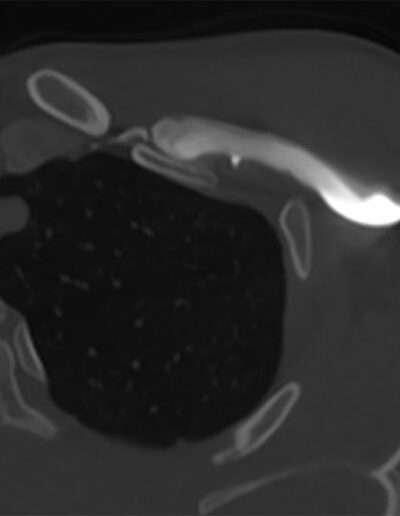

SHOULDER CASE SUMMARY:

| Shoulder | Left |

| Patient | 27 y/o, Female, right-handed |

| Profession/Sport | Gym manager / Body building |

| History | Painful shoulder and biceps |